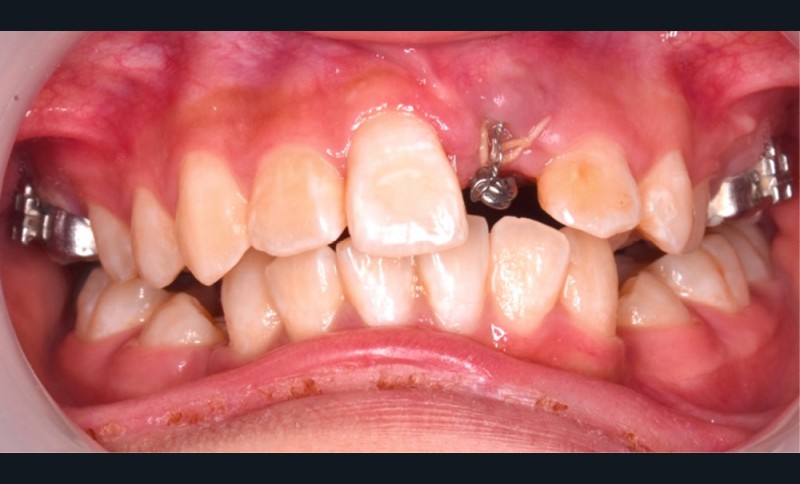

L’objectif du traitement est la correction de la DDA tout en assurant le remplacement de la 21 compromise. Décision a été prise d’extraire 34 et 44, ainsi que 21 et 14. La traction de la 23 a été réalisée à l’aide de forces légères, sur un arc transpalatin (fig. 9). Le nivellement et l’alignement, puis une mécanique par glissement ont permis d’aménager l’espace suffisant à la stratification de la canine. Elle associait un ressort en nickel-titane à des élastiques de Classe II (4 ½ oz, 3/16’’) sur un arc en acier .019×.025. Une phase d’ingression a été réalisée pour ajuster le niveau du bord libre de la canine à celui de l’incisive controlatérale (fig. 10-12).